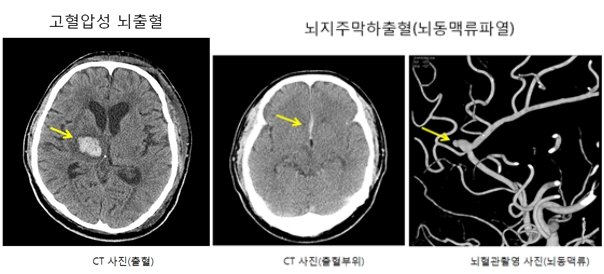

뇌출혈이 생기는 주요 원인으로는 ‘뇌동맥류’와 ‘고혈압’이 있다. 뇌동맥류는 뇌혈관의 일부가 비정상적으로 부풀어 오르는 질환으로 뇌출혈의 원인 중 30%를 차지한다. 혈관이 풍선처럼 부풀면서 터질 수도 있고, 터지면 ‘지주막하출혈’이라는 심각한 뇌출혈을 일으킬 수 있다.

고혈압성 뇌출혈은 뇌동맥류나 동정맥기형(출혈성 질환)과 같은 뇌혈관질환이 없더라도 고혈압으로 인해 뇌 안의 모세혈관들이 터지면서 발생하는 질환이다. 한순간에 반신마비가 되거나 의식불명, 사망까지 이르게 할 정도의 무서운 질환이라서 주로 발생하는 부위(호발부위)가 있지만 뇌 전반적으로 발생할 수 있다.